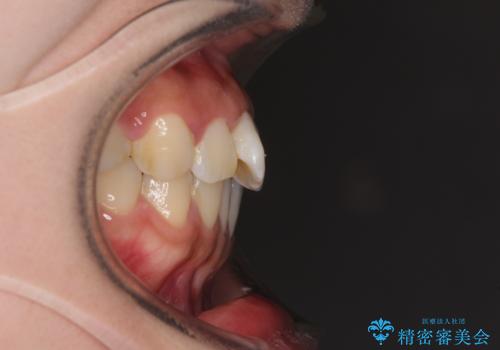

- 上顎歯列と下顎前歯の叢生を気にして来院された患者様です。

上顎からワイヤー矯正を開始し、終了間際から下顎前歯の叢生解消するよう計画しました。

部分矯正でしたが、咬み合わせに違和感が出ることなく気になる部分を改善させることができました。